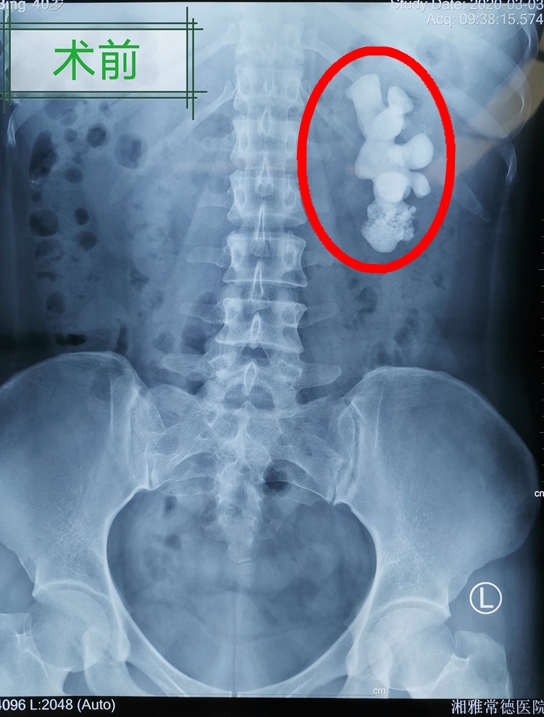

40岁的郭女士,20多年前查出患有肾结石。因害怕做手术,一直没有复查与处理。今年3月初,郭女士突然发现自己的尿液变红,出现血尿,特地前往长沙做了检查,一看结果吓一跳:原来左肾结石已...